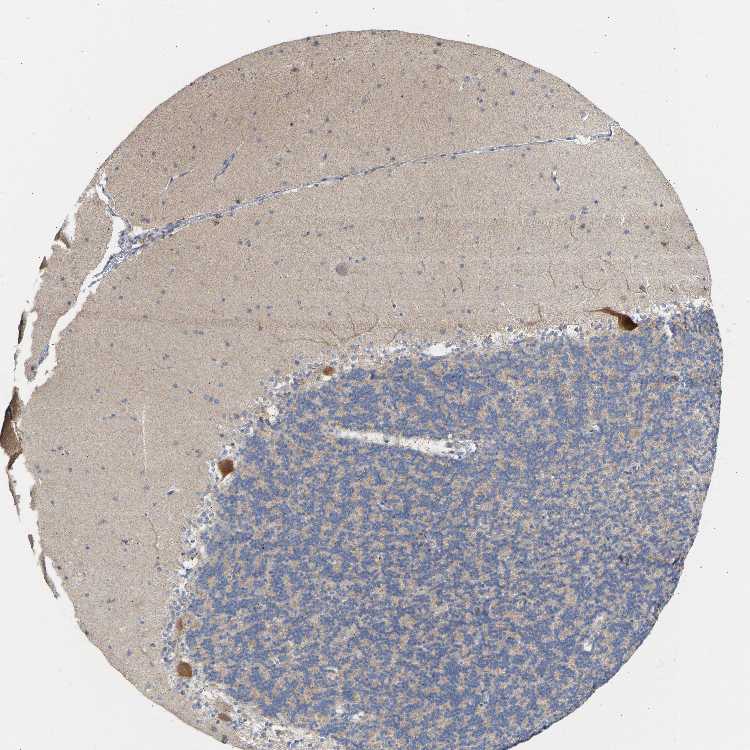

BRAIN CEREBELLUM Show tissue menu

CEREBELLUM - Antibody stainingi

Antibody staining in the annotated cell types in the current human tissue is reported as not detected, low, medium, or high, based on conventional immunohistochemistry profiling in selected tissues. This score is based on the combination of the staining intensity and fraction of stained cells.

Each image is clickable and will lead to virtual microscopy that enables deeper exploration of all samples and also displays staining intensity scores, fraction scores and subcellular localization as well as patient and tissue information for each sample.

Antibody HPA019851Antibody HPA062364

Purkinje cells - cytoplasm/membrane Medium-

Purkinje cells - dendrites Medium-

Purkinje cells - nucleus Not detected-

Granular cells - cytoplasm/membrane Medium-

Granular cells - nucleus Not detected-